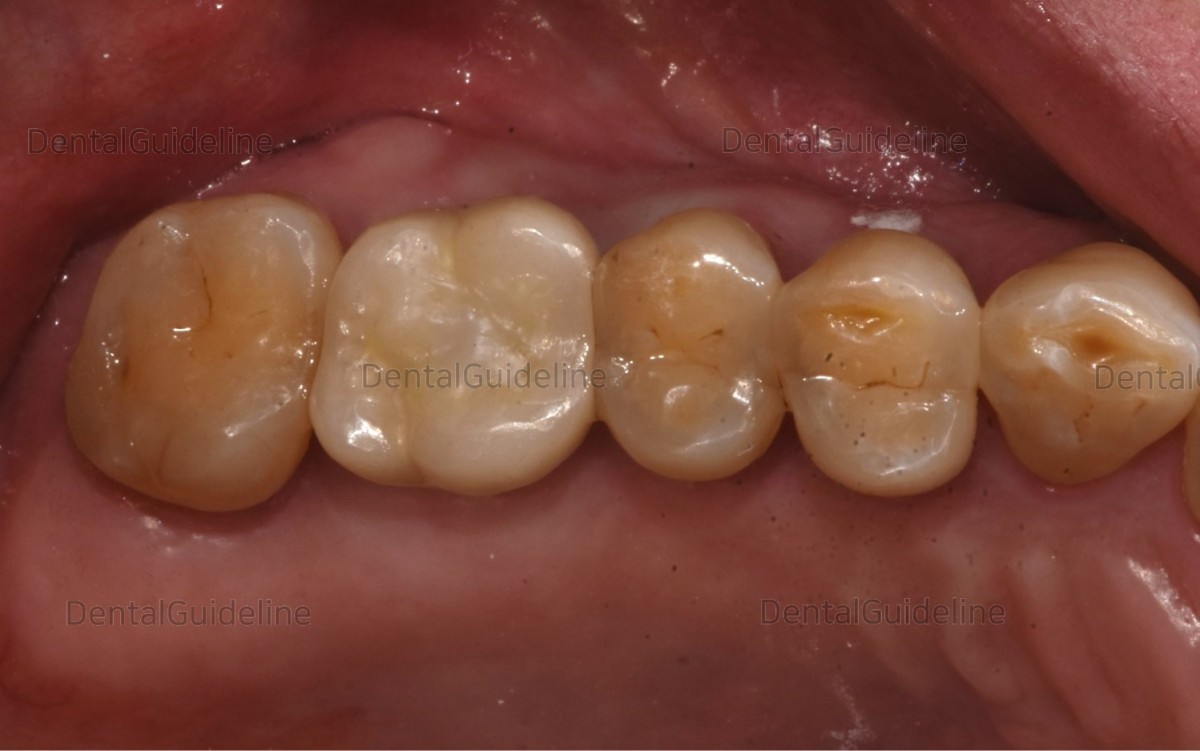

13. Implant crown seating. ![]()

14. Permanent cementation. The access hole was filled with composite resin.